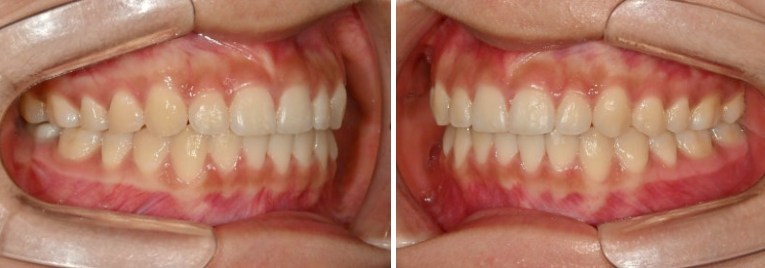

24년 여름방학을 이용해서 교정상담을 온 유학생 환자분입니다.

측절치의 개방교합, 아래 앞니 덧니 등 보입니다.

우측 교합관계는 1급에 가깝지만

좌측 교합관계는 2급입니다.

위 아래 치아들이 일대일로 물리면 2급 또는 3급 교합관계 입니다.

치료시작 11개월 차, 첫 세트의 48개 장치를 모두 낀 후 모습입니다.

중심선이 아직 약간 어긋나 있지만 덧니와 개방교합은 개선되었습니다.

좌측의 2급 교합이 아직 남아있습니다.

중심선은 맞아졌고

어금니 교합은 좌우 모두 1급 교합관계를 달성

이제 전 후 비교 보겠습니다.

총 치료기간은 1년 4개월 입니다.